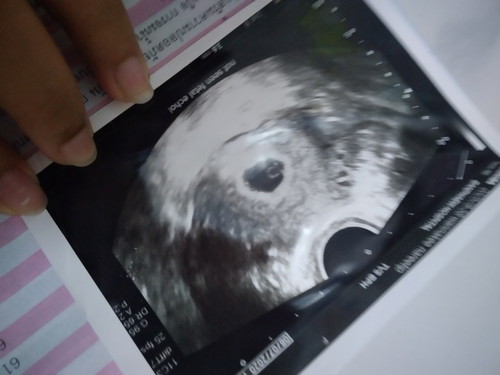

มีใครเคยไปซาวด์ครั้งแรกไม่เจอน้องบ้างคะ

หมอบอกเจอแต่ถุงตั้งครรภ์หมอบอกน้องยังเล็กมาก แอบกลัวจังเรยค่ะ

ปกติค่ะ บ้านนร้ตอนไปซาวด์ครั้งแรกก้ไม่เจอ ตอน6วีค บางคนก้ไปซาวด์ตอน8-9วีคก้เจอเลย แต่บ้านนี้รอไปซาวด์ตอน12วีคค่ะ

ปกติค่ะของครรภ์อ่อนค่ะ เด๋วไปรอบต่อไปก้เจอค่ะ